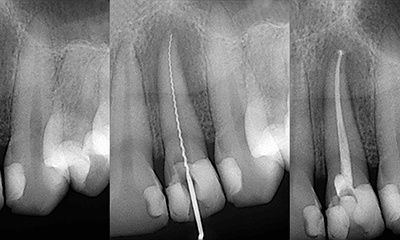

Root Canal Treatment

Root Canal Treatment is a procedure performed on the infected tooth to remove the decay affecting the pulp (underlying tissue containing blood vessels and nerve supply to a tooth). Simple filling procedure cannot restore a tooth’s dental health when the infection has encroached the pulp. Root canal therapy is the only alternative to save such tooth from being extracted. The main objective of root canal treatment is to preserve the infected existing natural tooth by disinfection. During a root canal therapy, access to the root canal present inside the root of a tooth is gained and the infected tissue is removed entirely. Hence Root Canal treatment bypasses extraction of the infected tooth and its replacement procedures thereby saving time and money.